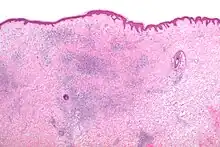

Microscopic appearance

Skin biopsies are not indicated for bites or stings, since the histomorphologic appearance is non-specific. Bites and stings as well as other conditions (e.g. drug reactions, urticarial reactions, and early bullous pemphigoid) can cause microscopic changes such as a wedge-shaped superficial dermal perivascular infiltrate consisting of abundant lymphocytes and scattered eosinophils, as shown in the adjacent figure:[12]